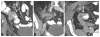

The appendix may demonstrate a perplexing range of normal and abnormal appearances on imaging exams. Familiarity with the anatomy and anatomical variants of the appendix is helpful in identifying the appendix on ultrasound, computed tomography, and magnetic resonance imaging. Knowledge of the variety of pathologies afflicting the appendix and of the spectrum of imaging findings may be particularly useful to the emergency radiologist for accurate diagnosis and appropriate guidance regarding clinical and surgical management. In this pictorial essay, we review appendiceal embryology, anatomical variants such as Amyand hernias, and pathologies from appendicitis to carcinoid, mucinous, and nonmucinous epithelial neoplasms.